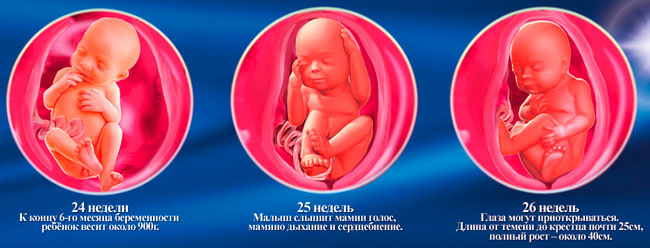

25 недель беременности: Как выглядит будущий малыш

Раздел: Образы вокруг